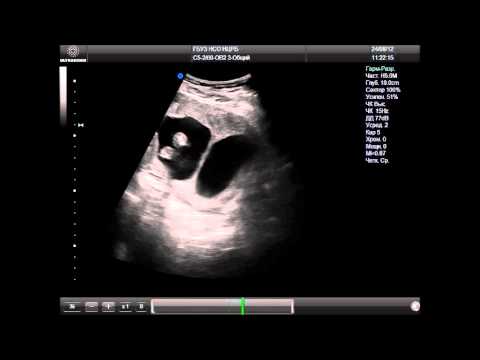

Ультразвуковое исследование

Метод не всегда способен точно выявить патологию. На ультразвуковом исследовании внутриматочная перегородка представляется как тонкая структура, расположенная в переднезаднем направлении. Различить двурогую матку и перегородку с помощью этого метода бывает довольно трудно.

Иногда специалисты обнаруживают внутриматочную мембрану в первом триместре, но при последующих обследованиях аномалия уже не фиксируется. Что это может означать? Вероятнее всего, произошел естественный разрыв тонкой перегородки в результате роста плода.